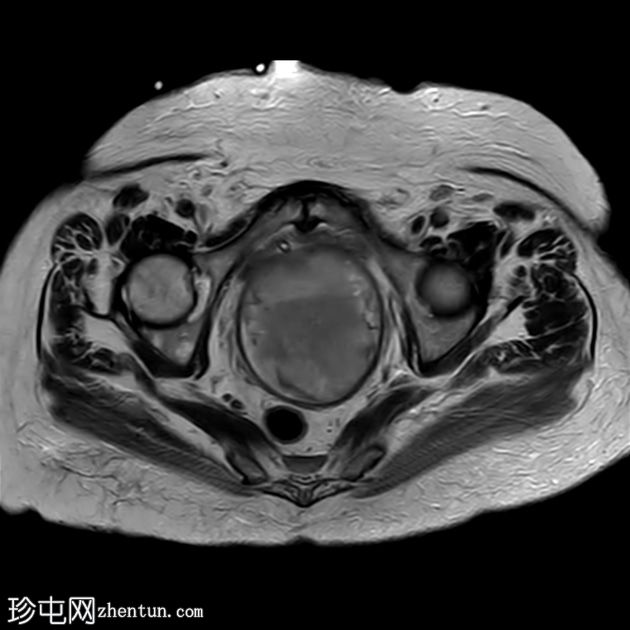

轴位

T2

子宫呈U形,宫底轮廓消失,宫底突出至扩张的阴道内,宫颈位于内翻的宫底上方(II级子宫内翻):

宫底处可见阴道内可见边界不清、分叶状实性肿块,明显扩张阴道壁,阴道壁完整。

肿块最大轴向及头尾径约为 9.7 x 9.6 x 9.5 cm,T1 加权像呈低信号,T2 加权像呈中/高信号,伴有扩散受限和不均匀增强。

肿块前方压迫膀胱,后方紧邻乙状结肠,未见侵犯。

肿块压迫左侧远端输尿管,导致轻度输尿管肾积水。

矢状位MRI:显示子宫呈U形,正常的凸形宫底轮廓消失。

轴位MRI:可能显示靶环状或同心环状结构,提示子宫内膜存在不同层次。